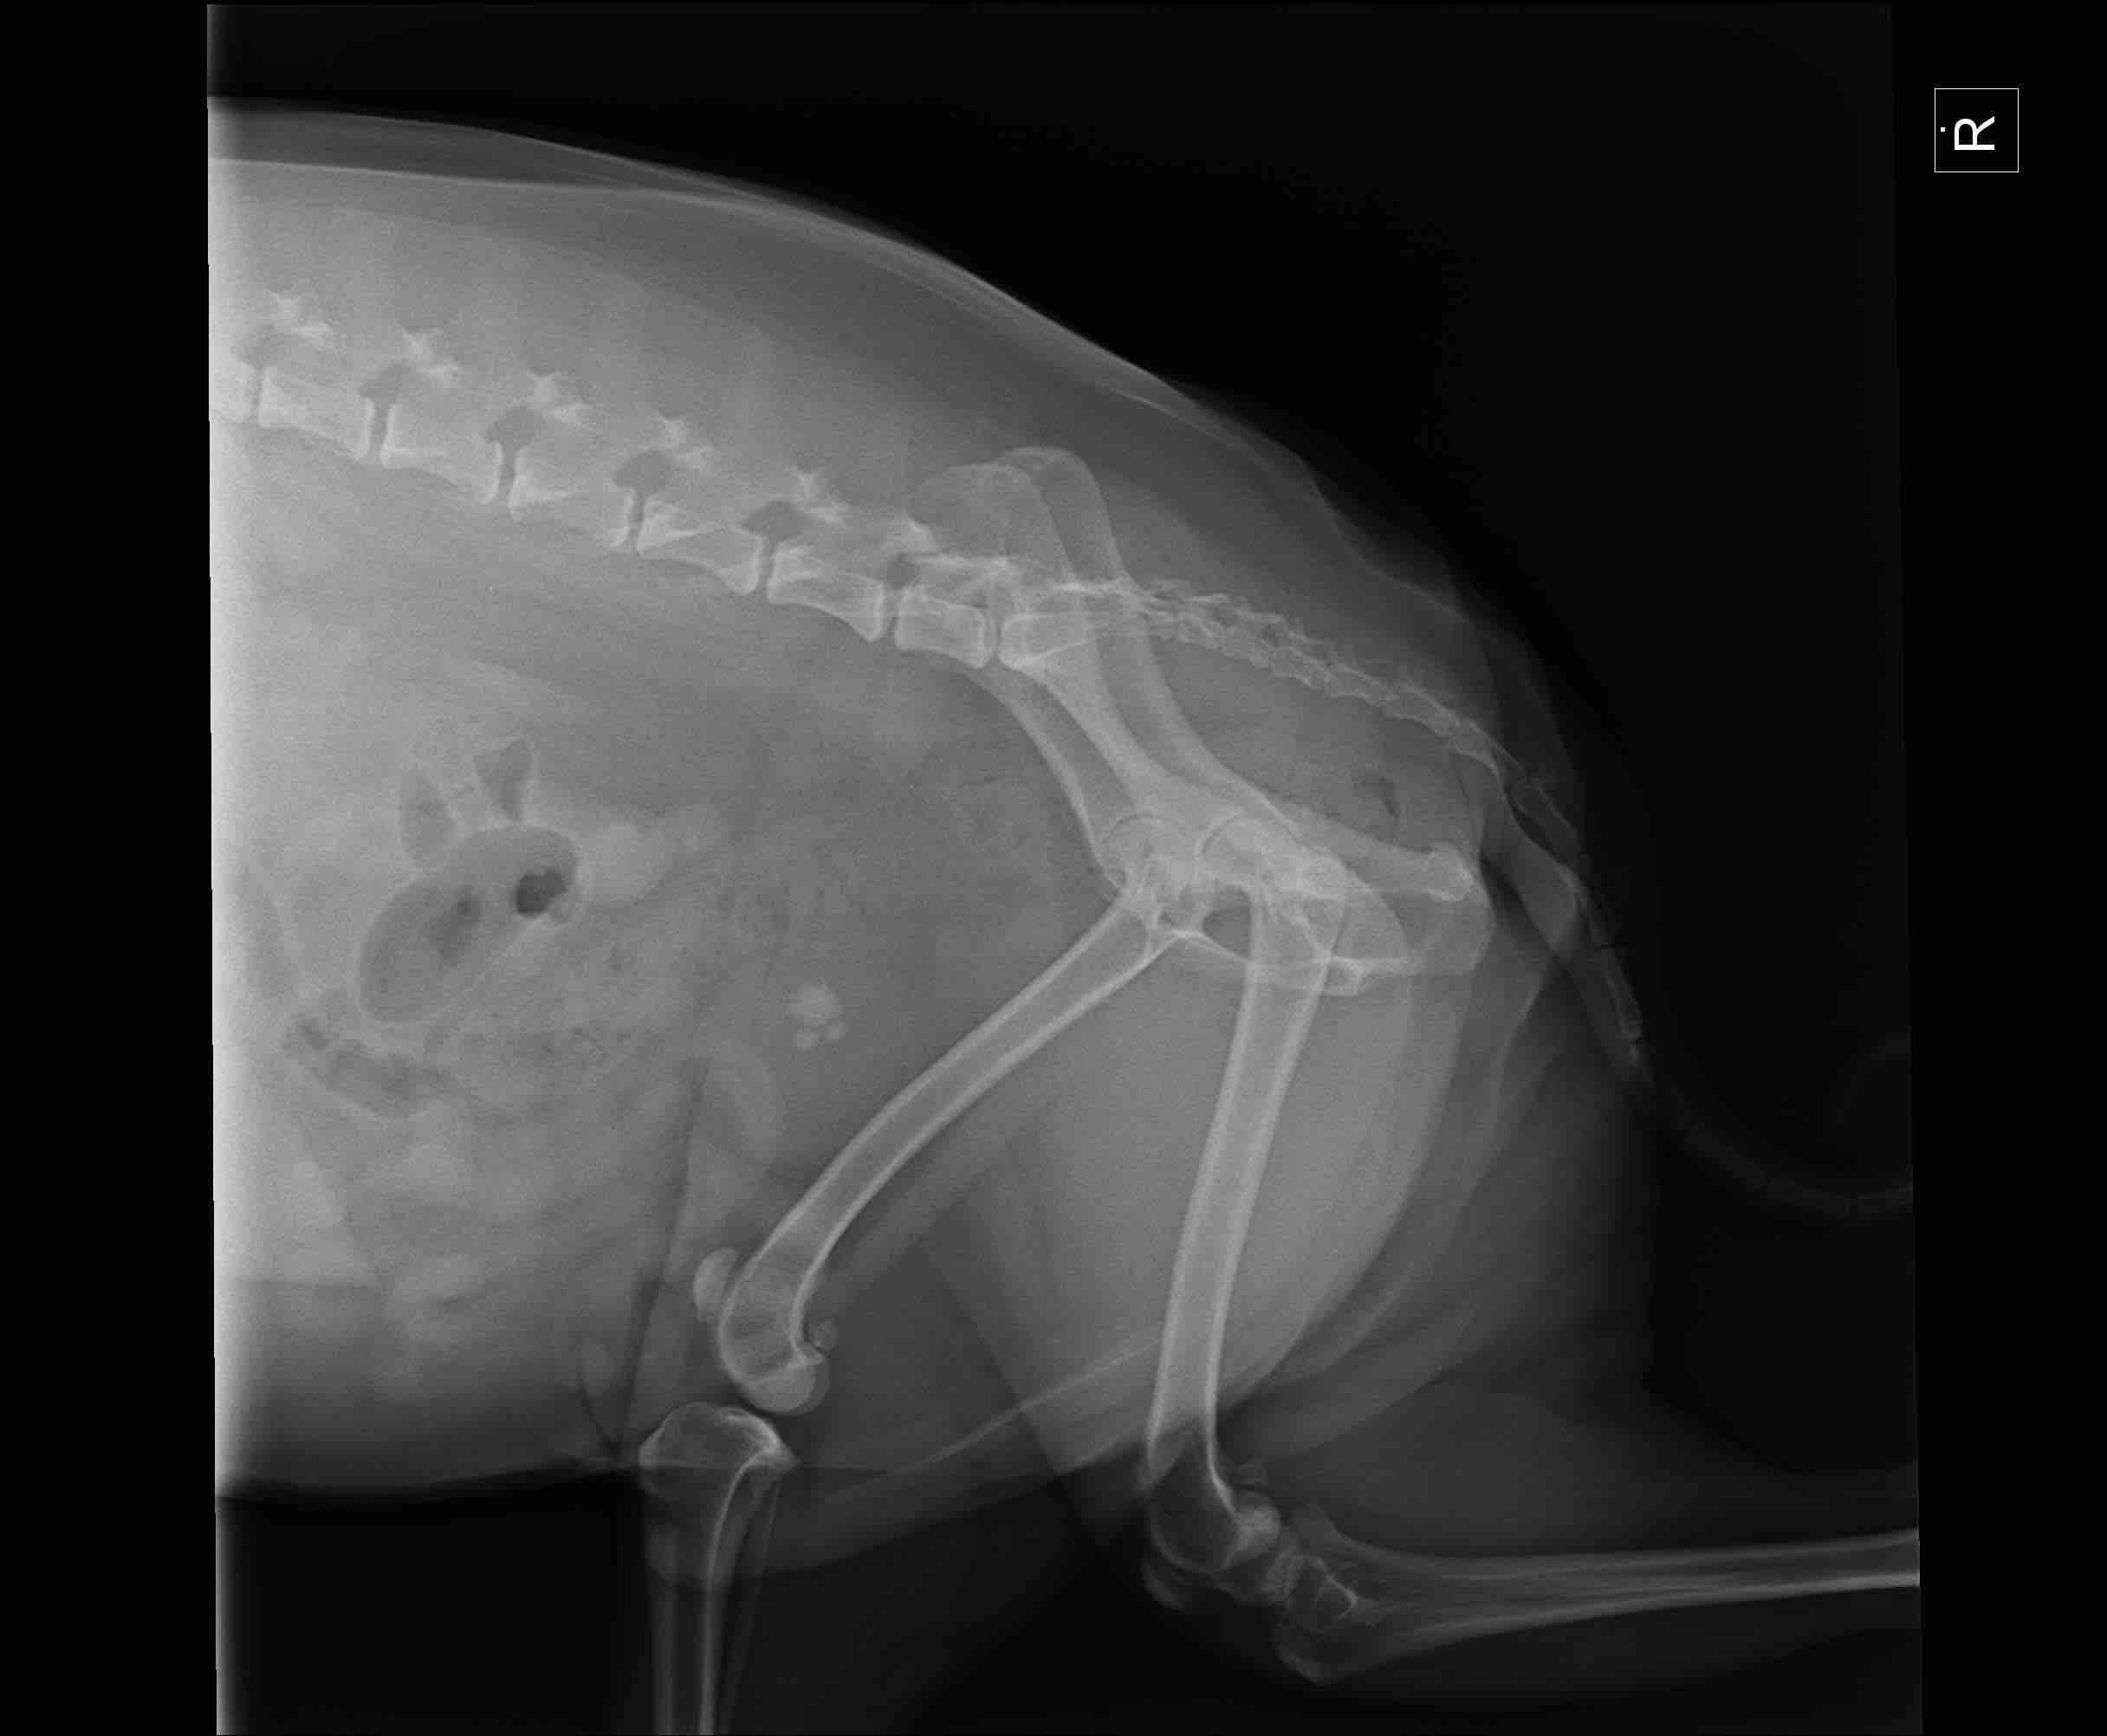

Brody has been having lameness in his hind legs. He was put on meds for inflammation and it still continued. Went back for X-ray. Vets seem to think arthritis. We then started him on dasuquin three weeks ago. He is still experiencing lameness in his hind legs. Should he be showing improvement by now if it is arthritis? Also xrays did show bladder stones which i understand can cause pain in abdomen. Could it present as leg pain to us? I’m attaching his X-rays. Should i seek second opinion? Thanks

I hate to hear that Brody is experiencing some issues with his legs. I agree that the hips look like they could be the source of the lameness with decreased acetabular coverage of the femoral heads and also a slight thickening of the femoral necks. I do not anticipate lameness from the bladder stones. Discomfort from the bladder stones tends to occur when Brody urinates and I have seen some pets exhibit no signs. You may discuss with the veterinarian ways to address the stones as they can cause problems with urinary tract infections or even cause obstruction of the urethra. Most pets will have surgery although depending on the type of stone, some may be able to break down with a special diet. Regarding the lameness, Dasuquin is a good product and it will take 4-6 weeks to reach maximum strength. Most vets recommend loading the supplement (so they take a higher amount for 4-6 weeks) then they decrease it. Give it a little more time to take effect. Other things that can help with arthritis including giving an additional omega 3 fatty acid (Nutramax makes a nice product) can help with natural inflammation control. There is another product I like called Duralactin and it is a joint supplement that I often use in conjunction with Dasuquin. If you are interested in a diet change, Royal Canin makes a diet called Mobility Support which has green lipped muscle as an ingredient and pets tend to do very well in it. Lastly, you make consider seeking a veterinarian or facility who can offer physical therapy. Especially with the hind legs, muscle mass and tone is very important in stabilizing the joints. Daily, low impact activity is very important in maintaining this. A physical therapist will examine the lameness and all the muscle groups and will show you exact exercises you can do at home to maintain optimal muscle health. Long term, this is very important. Sometimes the therapist will recommend other things like working on an under water treadmill, swimming or even acupuncture to help. It’s definitely beneficial to get therapies started early while the signs are still mild. Certainly if Brody does not respond well after 6 weeks, I think seeking a second opinion is valid. I hope this helps and thank you for using Petco Pet Education Center, formerly Petcoach.